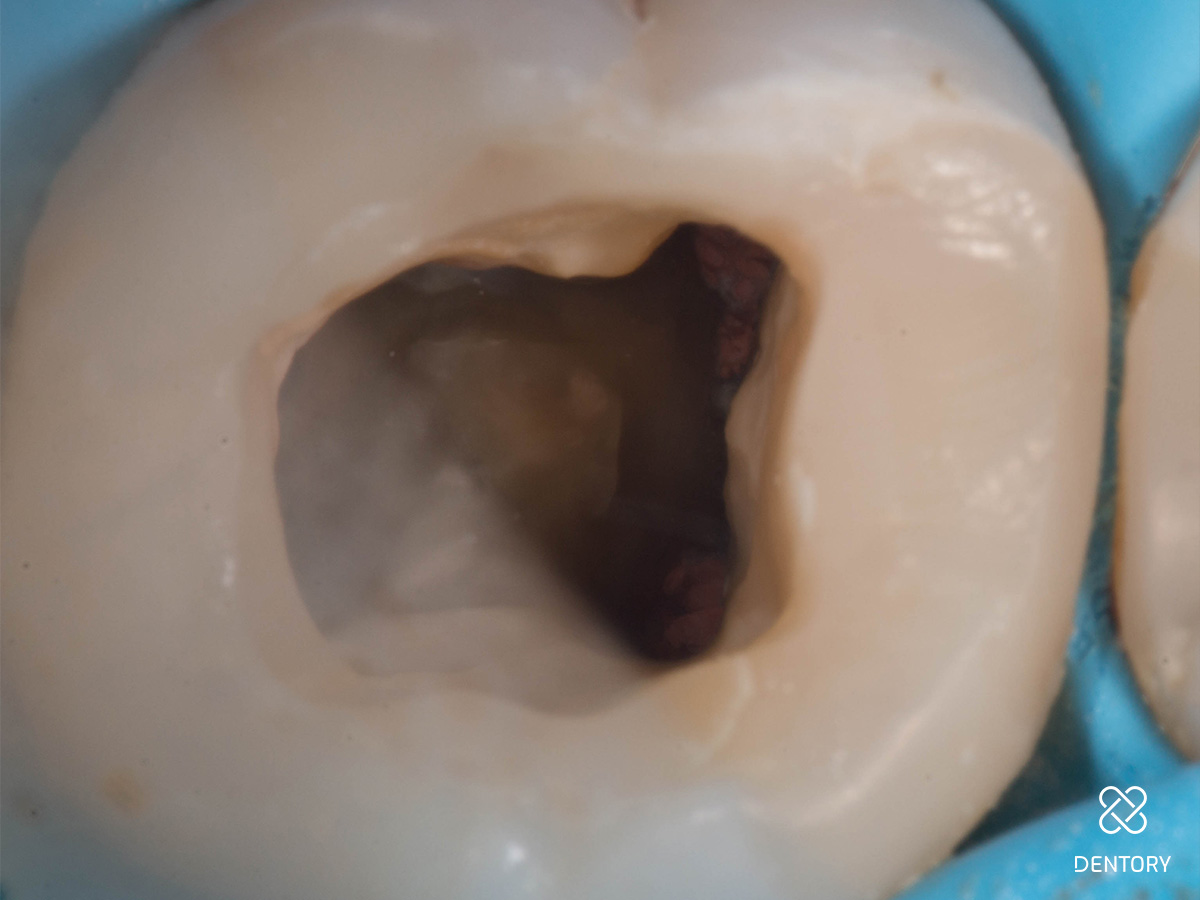

Abbildung 1

Ausgangssituation: Das initiale Röntgenbild zeigt den Grund für die Schwellung.

Abbildung 2

Entfernung der insuffizienten Füllung. Man kann erkennen, dass die Guttapercha aufgrund der hohen Transluzenz des damals verwendeten Materials durch die Füllung scheint.